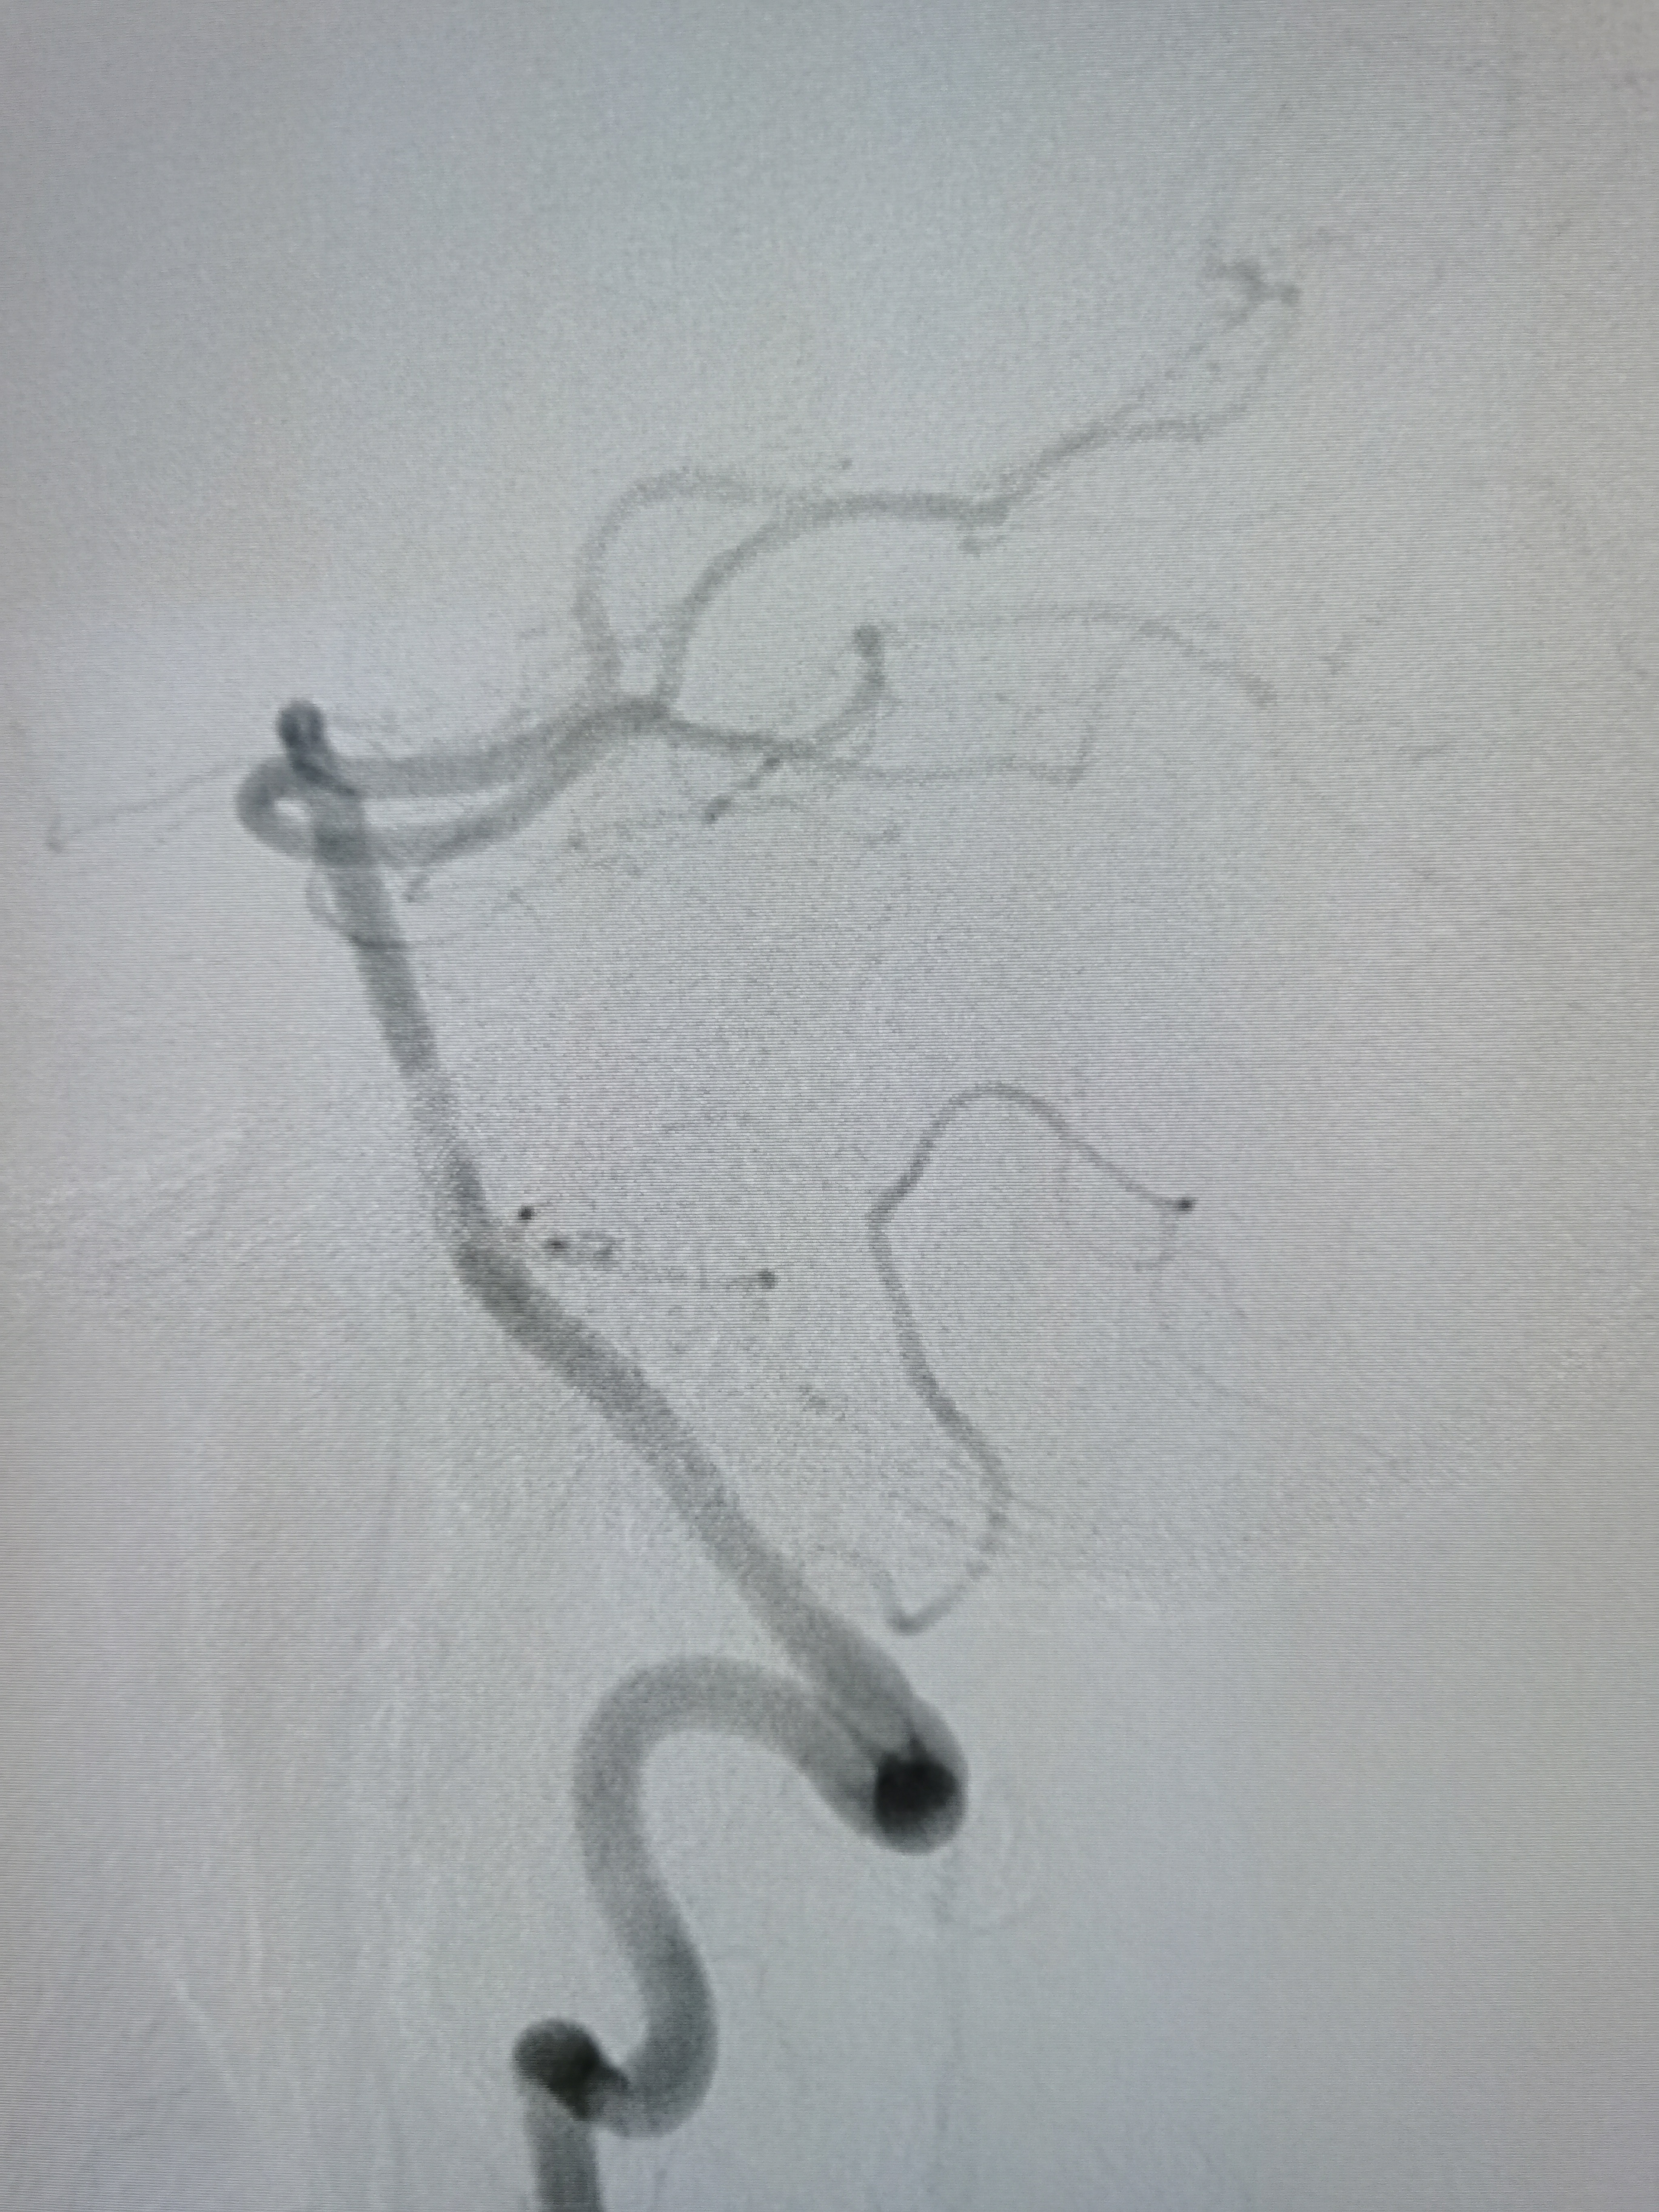

右侧颈内动脉起始部重度狭窄。

颅内段显影可。

右侧孤立大脑中动脉,M1轻度狭窄。